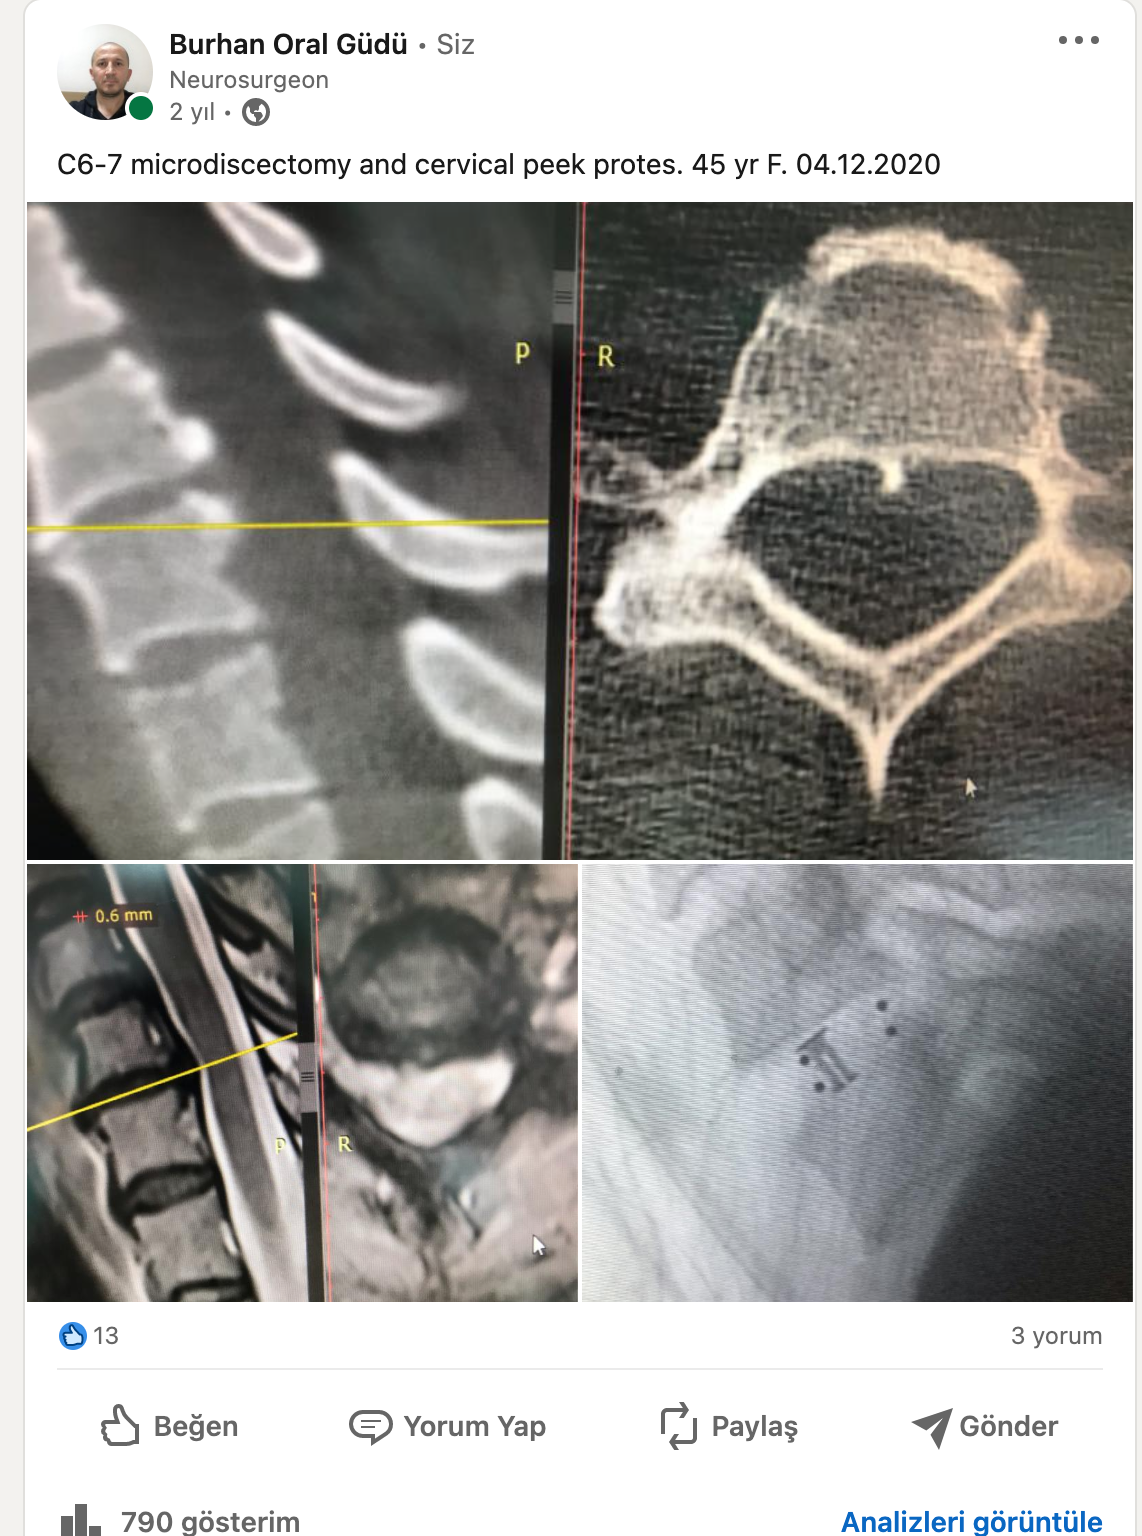

Bel fıtığı bilgi

Siyatik